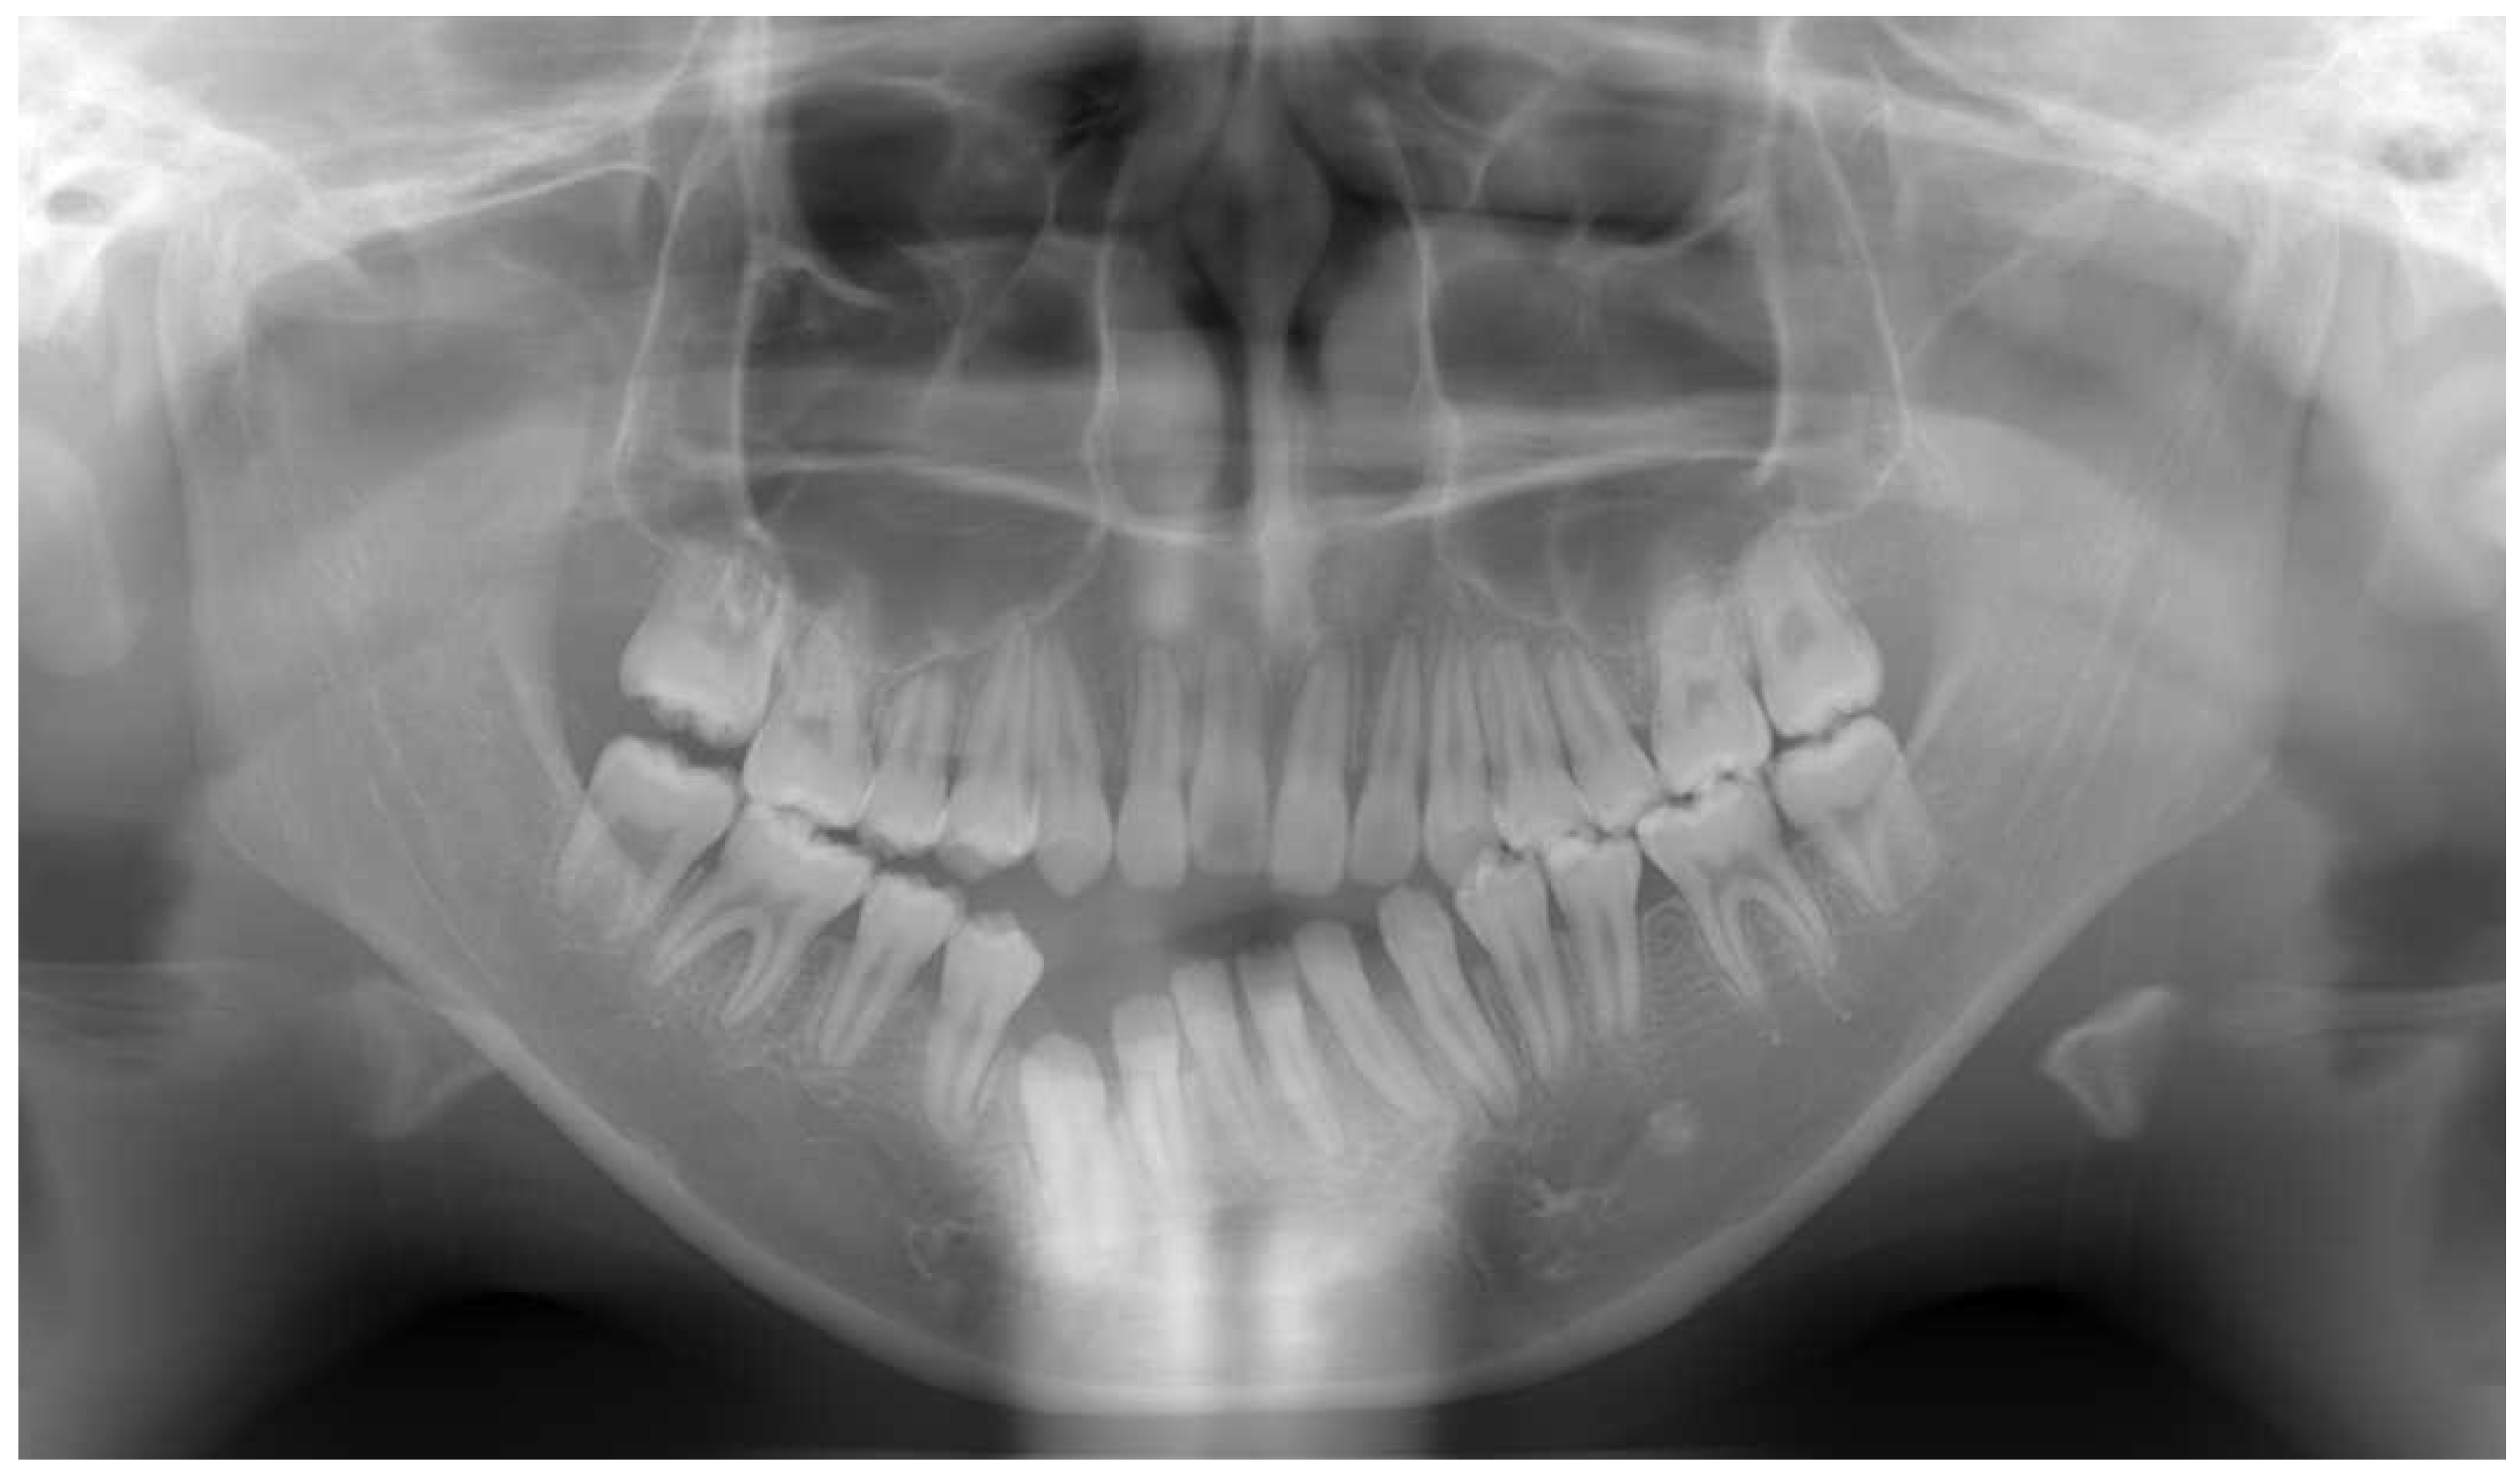

2.6. Imaging Examinations

2.7. Diagnosis